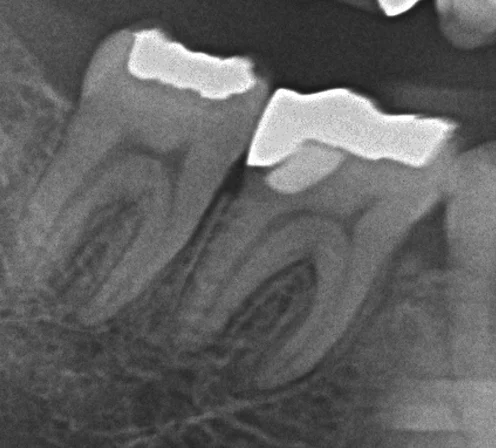

レントゲンで見ると奥2本が非常に大きな虫歯になってしまっています。

神経へのダメージも十分に考えられる状況でしたので、2日に分けて1本ずつ処置に入りました。

まずは1本目。